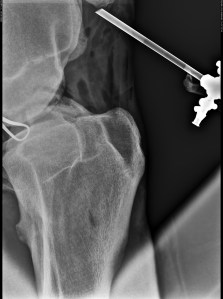

I spent as much time with him as I possibly could. When his joint was so painful, I stood next to him and tried to support his right side with my arms under his belly, so he could relax his back muscles a bit which were all cramped from the pain. He started to walk around the box, me still holding his side and trying to carry as much of his weight as possible. Like this he was able to move around a bit. Some time later he looked at his right side, I took the hint and helped him again, and like this we walked around the box a few times an hour until he was better two days later. I brought him fresh grass from outside, sat in his box and read, massaged him a bit. When the trailer pulled up in front of the clinic to bring him home, I lead him out of the stable for the first time in 10 days. He stopped, looked around, and took a deep breath. We had him in the trailer in no time, although he’s usually not that fond of loading. On the last meters before home, he called out to his friends again and again. You should have seen how happy he was to be back home. For five weeks, he stayed in his box and a small paddock the size of his box. Twice a day, me or the stable groom walked him for fifteen minutes. Thanks to the joint supplements I gave him his joint soon looked normal again. I even had a feeling that he walked much better, more elastic. He wasn’t on his best behaviour, but I thought that was quite normal under the circumstances and I didn’t hold it against him. He was still easy to manage though. I had to go to Germany for three weeks and was very happy to leave him in such good hands. Then, on the 28th of July, we made x-rays to see if this fragment was still visible. The joint looked absolutely fantastic and I had a slight hope that this fragment would be situated in a place where it wouldn’t disturb and we wouldn’t need another operation. Of course it was the exact opposite, as you can see here:

Dr Samsel had promised to do the next operation for free (I think that happens only in Poland…), so I called him and we arranged for me to bring Nazir to the clinic again. Nazir didn’t really want to go in the box at the clinic and wasn’t very friendly to me the next days. I wonder if horses can hold a grudge. On September 4th, Dr Samsel performed the second arthroscopy. This time no complications occurred (phew) and they moved Nazir to another stable close to the clinic the day after the operation. The joint doesn’t even look that swollen. Nazir wasn’t very happy about moving stables at first. However,I thought the other stable, although quite run down, is an improvement. At least he has a window to the outside and can see some other horses. It doesn’t smell of disinfectant and I can sit with him without getting strange looks from the employees (none of the other horses, about 25 of them, get regular visitors). After all these weeks, Nazir is not in a happy place. His eyes show clearly that he is suffering from his imprisonment. I can only tell myself that it’s for his best and that every day that’s gone by he’s closer to a normal life again, maybe an even better life than before. After all, there is a good chance that the arthritis will not return, now that the cause is removed. Below you can see two of the fragments by the way.